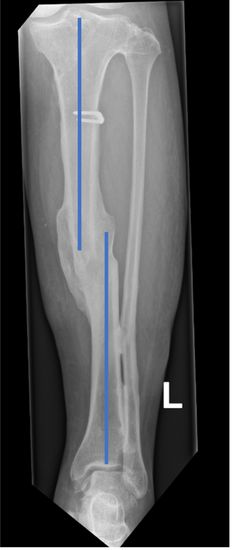

Bild: Universitätsklinik Balgrist

In der klinischen Untersuchung werden die Schmerzen lokalisiert und meist schon die Fehlstellungen erkannt. Wichtig dabei ist, auch auf mögliche Muskelverkürzungen zu achten. Röntgenbilder helfen, die Fehlstellung des Knochens zu erkennen. Dabei ist es wichtig, immer mindestens zwei Ansichten (Bilder in 2 Ebenen, gerade und seitlich) aufzunehmen, die möglichst senkrecht aufeinander ausgerichtet sind. Ansonsten erkennt man z. B. in einem seitlichen Röntgenbild nicht, wie sich die Fehlstellung von vorne betrachtet darstellt.

Eine genaue Analyse der Fehlstellung gelingt nur mittels dreidimensionaler Bildgebung. Das derzeit etablierte Verfahren dazu ist ein Schichtröntgen (Computertomographie – CT) des Unterschenkels. Mit Hilfe von an der Universitätsklinik Balgrist entworfenen Programmen, sind wir in der Lage, mittels CT ein dreidimensionales Modell des Beins zu erstellen *. Ein gespiegeltes Modell des anderen, gesunden Beins kann als Vorlage für das Bein mit der Fehlstellung dienen *.